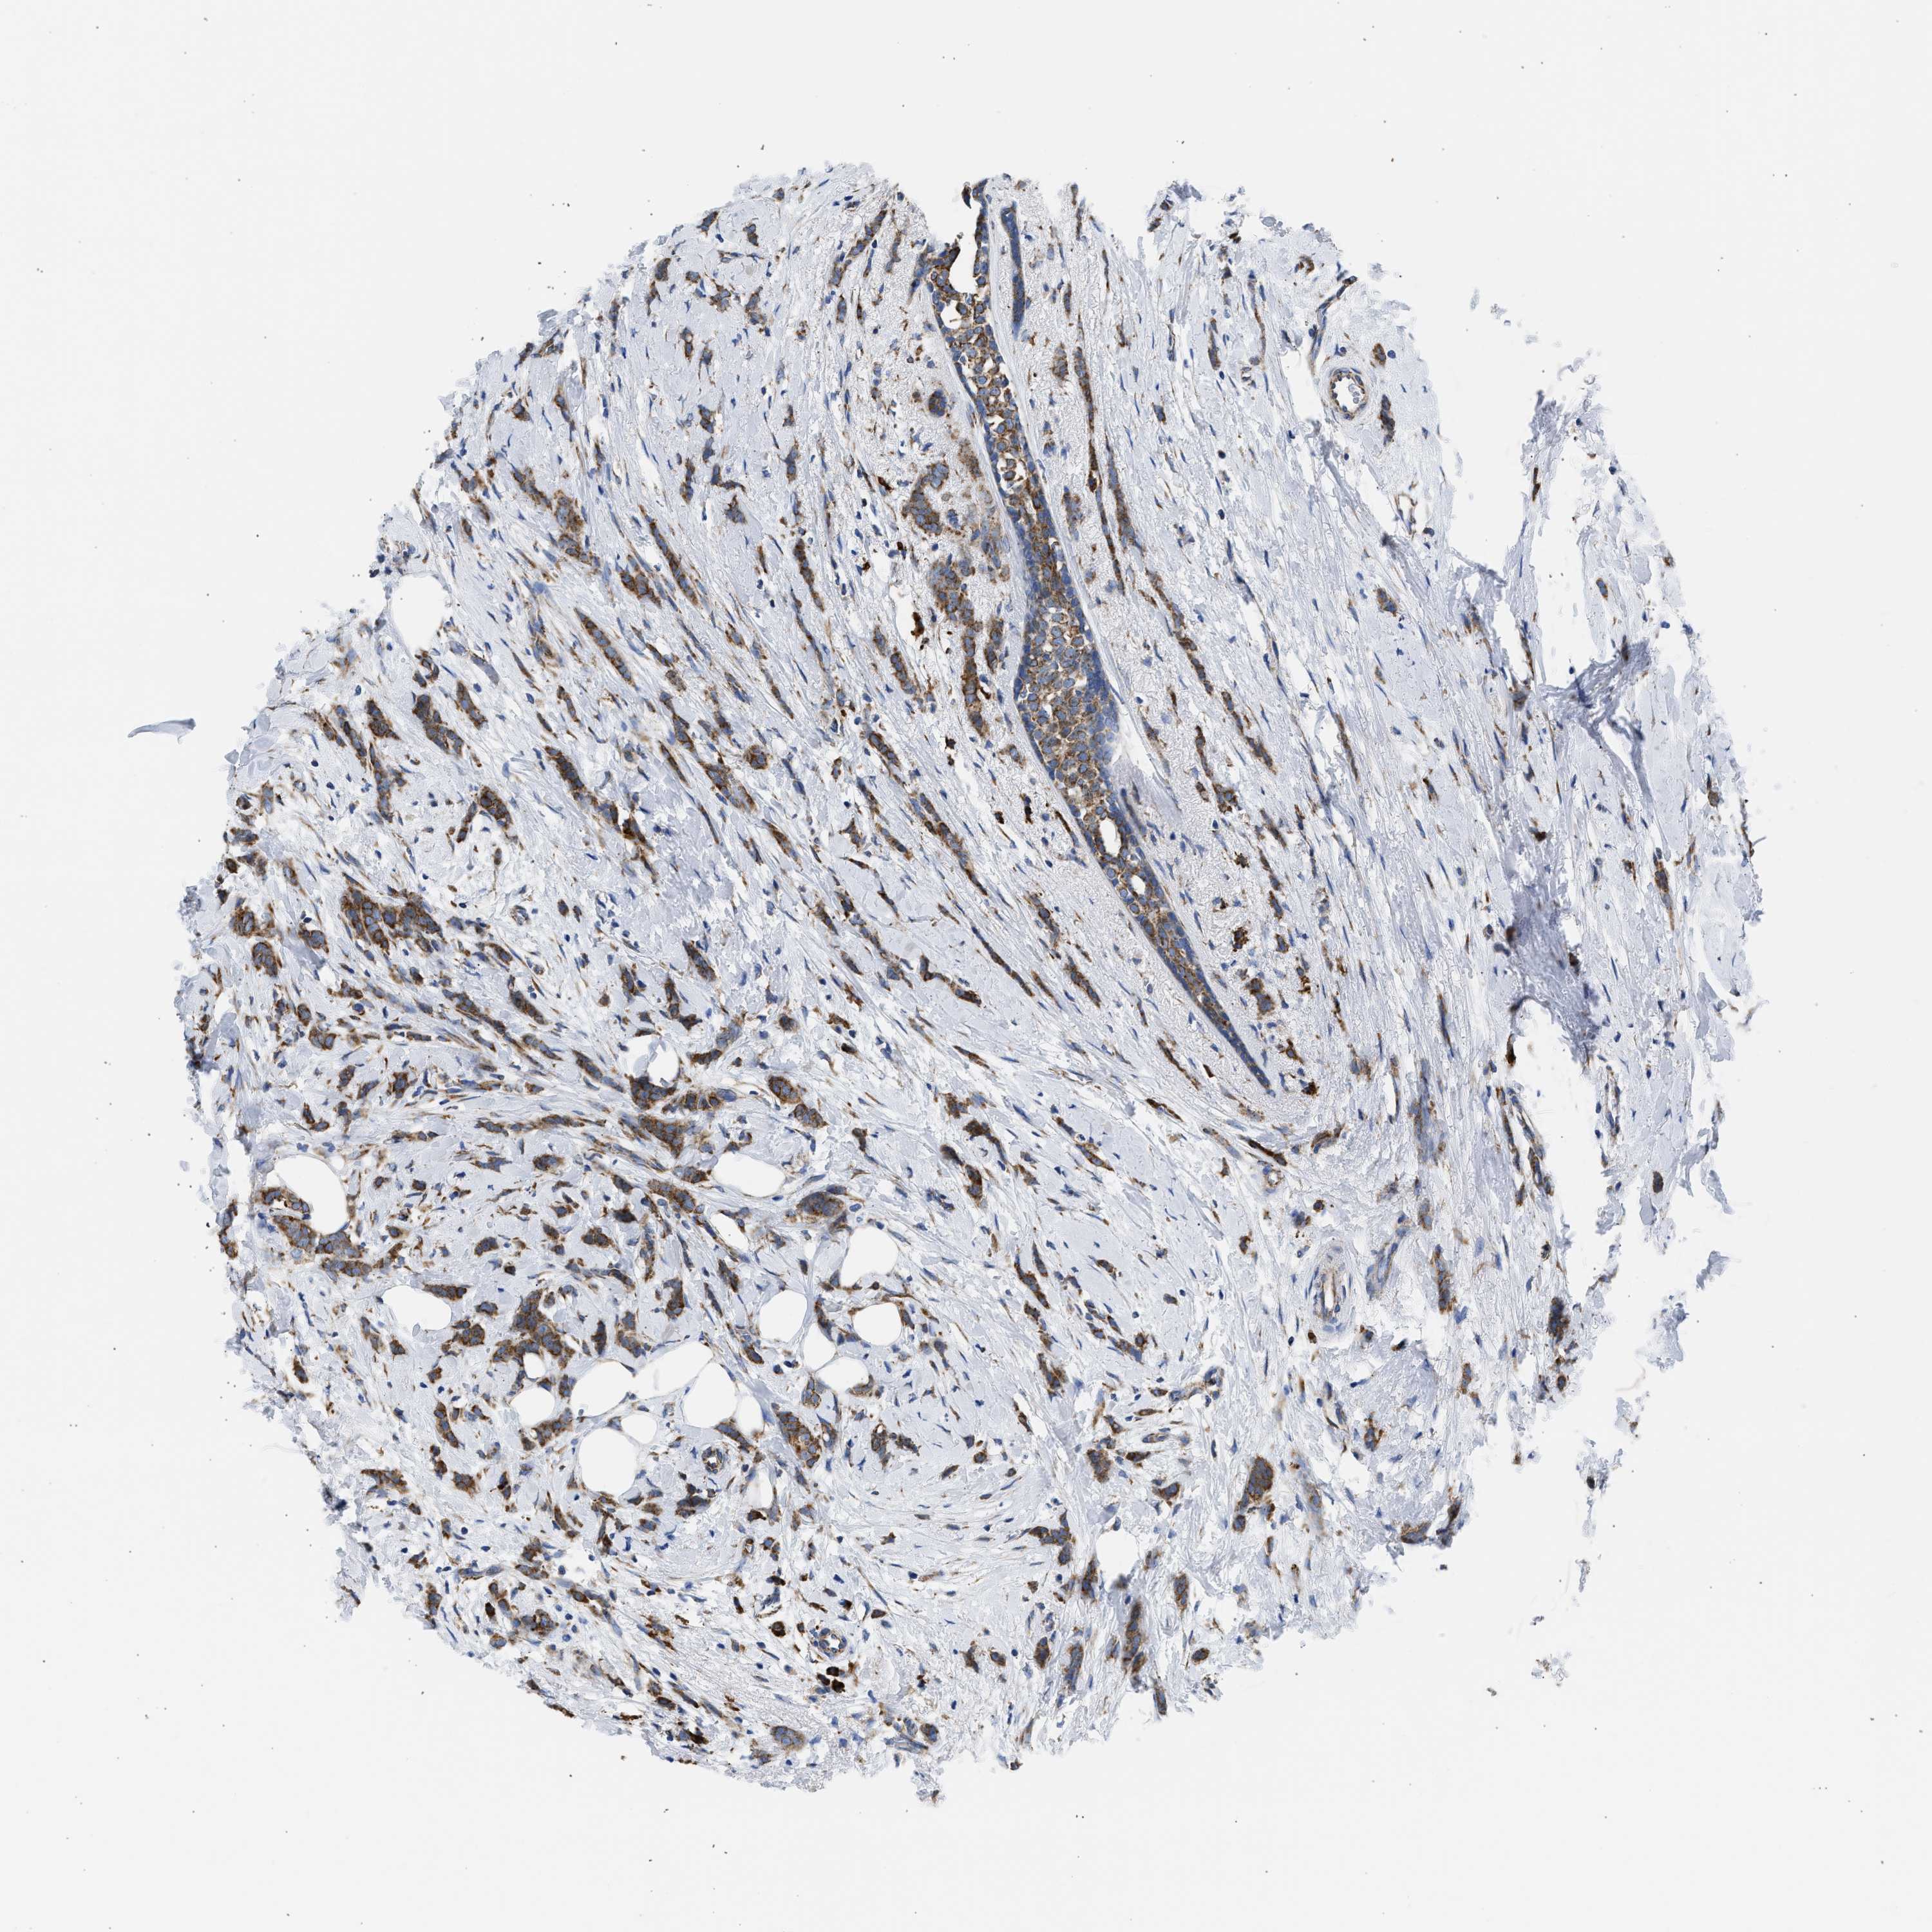

BRCA TCGA BRCA VALIDATION PROTEIN EXPRESSION